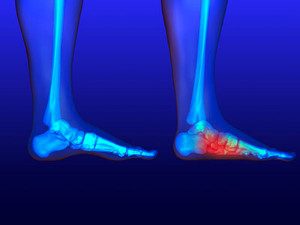

Plantar fasciitis is a painful foot condition that is typically felt after taking your first steps in the morning. The symptoms tend to go away when you sit down, but the sharp pains will pop up again when you walk around. Some risk factors for the condition include standing for a long period of time, increased body weight, and age. The best way to alleviate plantar fasciitis pain is to treat the condition in its early stages instead of waiting for it to progress. You should contact your podiatrist immediately if you suspect you may have plantar fasciitis in order to get rid of any pain you are experiencing.

Plantar fasciitis is a painful foot condition that is typically felt after taking your first steps in the morning. The symptoms tend to go away when you sit down, but the sharp pains will pop up again when you walk around. Some risk factors for the condition include standing for a long period of time, increased body weight, and age. The best way to alleviate plantar fasciitis pain is to treat the condition in its early stages instead of waiting for it to progress. You should contact your podiatrist immediately if you suspect you may have plantar fasciitis in order to get rid of any pain you are experiencing.

Plantar fasciitis is the inflammation of the thick band of tissue that runs along the bottom of your foot, known as the plantar fascia, and causes mild to severe heel pain.

Read more about Blisters on the Feet Plantar fasciitis is one of the most common causes of heel pain that podiatrists see in their patients. Plantar fasciitis involves the irritation or inflammation of the plantar fascia, which is a thick band of tissue located on the bottom of the foot that supports the arch and connects the heel to the toes. Irritation and inflammation typically occurs after overusing or overstretching the fascia, creating symptoms of pain. Wearing shoes that are not appropriate for the physical activities you engage in can also cause plantar fasciitis. Preventing plantar fasciitis involves properly stretching the feet and wearing shoes that suit the specific activities you may be performing that day.

Plantar fasciitis is one of the most common causes of heel pain that podiatrists see in their patients. Plantar fasciitis involves the irritation or inflammation of the plantar fascia, which is a thick band of tissue located on the bottom of the foot that supports the arch and connects the heel to the toes. Irritation and inflammation typically occurs after overusing or overstretching the fascia, creating symptoms of pain. Wearing shoes that are not appropriate for the physical activities you engage in can also cause plantar fasciitis. Preventing plantar fasciitis involves properly stretching the feet and wearing shoes that suit the specific activities you may be performing that day.

Plantar fasciitis is the inflammation of the thick band of tissue that runs along the bottom of your foot, known as the plantar fascia, and causes mild to severe heel pain.